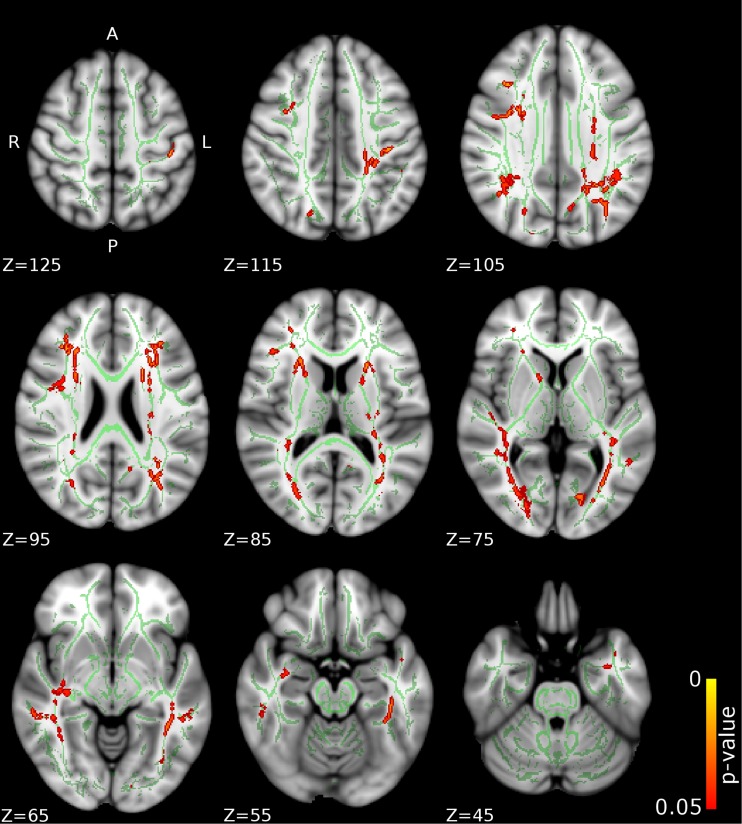

Fig. 1.

Differences in fractional anisotropy (FA) between the CD/CU+ and CD/CU- groups. The figure depicts increased fractional anisotropy in adolescents with Conduct Disorder with elevated callous-unemotional traits (CD/CU+) relative to those with Conduct Disorder with lower levels of callous unemotional traits (CD/CU-). The axial images are thresholded at p < 0.05, threshold-free cluster enhancement (TFCE) correction, i.e., correction for all voxels in the white-matter skeleton. Significance level of the findings is indicated by the red-yellow color scheme (with the most significant findings shown in yellow). All findings are superimposed on the mean FA background image and the outline of the TBSS-generated white-matter tract skeleton, shown in green

Compared to CD/CU- individuals, adolescents with CD/CU+ showed higher FA and lower RD and MD (indexing lower diffusivity) in commissural tracts (body and splenium of the corpus callosum), association tracts (right inferior longitudinal fasciculus, ILF; right inferior fronto-occipital fasciculus, IFOF; left superior longitudinal fasciculus, SLF) and projection/thalamic pathways (left cerebral peduncle, bilateral internal capsule, left superior and posterior corona radiata, bilateral thalamic radiation and left external capsule). Relative to the CD/CU- group, the CD/CU+ group also had lower RD and MD in most of the tracts mentioned above (see Figs. 1, 2, 3 and Table 2). Compared to the CD/CU- group, the CD/CU+ group also presented with lower RD and MD in left uncinate fasciculus and bilateral fornix (see Figs. 2 and 3 and Table 2).